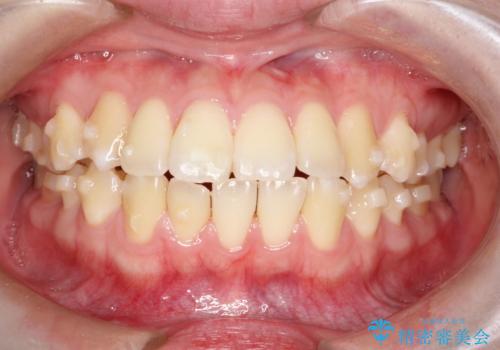

【インビザライン】歯を抜かずにできるだけ前歯を下げたい

- 前歯の前突を主訴に来院されました。

インビザライン を用いて、歯並びの改善を行うことができました。